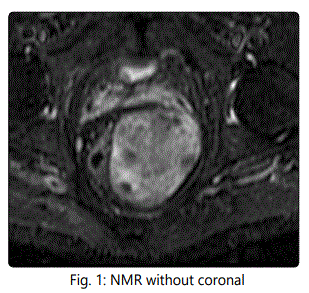

56-year-old man seen in consultation because of an injury on the left gluteus that causes discomfort. Magnetic resonance imaging of non-contrasting pelvis is performed for the diagnosis, which describes a large tumor with dimensions of 16 x 7 x 6 cm with well defined contours, lobed, located at the level of the ischiorectal fossa, displacing the elevator ani muscle and extending caudally towards the subcutaneous cellular tissue of the left gluteal region, without involvement of prostate, seminal vesicles and bladder. PAAF is guided by ultrasound and the pathological study shows fibroadipose tissue with vascular ectasia.

In our case the patient presents the tumor in perianal location. After the radiological study and biopsy, surgical treatment by means of a complete resection of Ligasure Impact tumor was chosen, observing a large tumor to the upper edge of the prostate. The preoperative anatomopathological results of fibroadiposal tissue with vascular ectasia differ from those analyzed by the surgical specimen resulting in atypical sclerosing lipomatous lesion with MDM2 expression in histology. This low-grade tumor is currently classified as a well-differentiated liposarcoma with poor metastasis and relapse after RO excision. The surgical treatment carried out does not manage to obtain free margins. After the patient's agreement with the treatment, he stated that he did not want to undergo surgical techniques, so no other resection was performed to expand the margins. Long-term observation of the patient is decided. After 12 months of follow-up he has not shown recurrence of the disease at present.